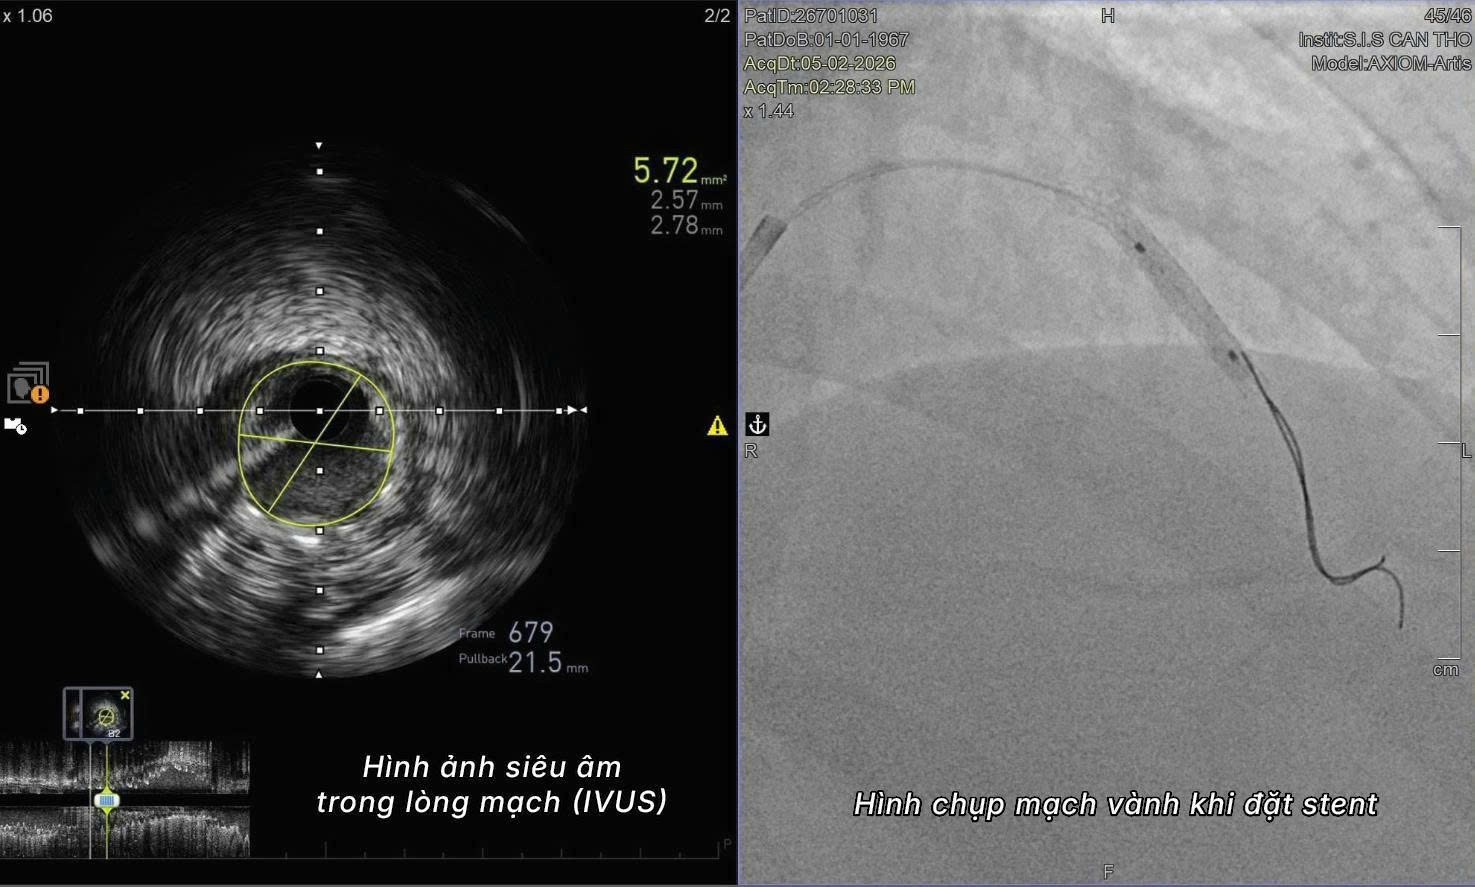

Bác sĩ Chỉnh cho biết trước đó bệnh nhân đã có dữ liệu hình ảnh CT mạch vành, giúp bác sĩ định hướng các mốc giải phẫu của hệ mạch. Trong quá trình can thiệp, thay vì bơm thuốc cản quang để quan sát lòng mạch, ê-kíp sử dụng siêu âm trong lòng mạch (IVUS) để nhìn trực tiếp cấu trúc bên trong động mạch và xác định chính xác vị trí tổn thương.

Nhờ hệ thống hình ảnh nội mạch này, các bác sĩ đã tiến hành đặt stent tái thông mạch vành thành công, khôi phục dòng máu nuôi tim cho bệnh nhân. “Đây là ca đầu tiên tại bệnh viện chúng tôi thực hiện can thiệp mạch vành hoàn toàn không sử dụng thuốc cản quang và cũng là một trong số rất ít trường hợp được ghi nhận tại Việt Nam”, bác sĩ Chỉnh cho biết.

Theo các chuyên gia tim mạch, IVUS (Intravascular Ultrasound – siêu âm trong lòng mạch) là kỹ thuật sử dụng đầu dò siêu âm siêu nhỏ đưa trực tiếp vào lòng động mạch, cho phép bác sĩ quan sát toàn bộ cấu trúc thành mạch, mức độ hẹp và vị trí tổn thương từ bên trong lòng mạch.

Khác với phương pháp chụp mạch vành truyền thống phụ thuộc vào thuốc cản quang để tạo hình ảnh gián tiếp, IVUS cung cấp hình ảnh chi tiết theo thời gian thực về lòng mạch, giúp bác sĩ đánh giá chính xác vị trí đặt stent cũng như mức độ mở rộng của stent sau can thiệp.